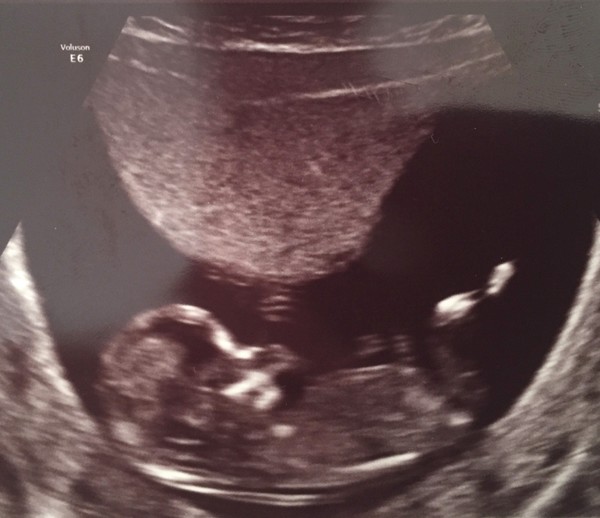

MissMartin10 · 06/07/2015 18:02

Wow kep what lovley clear pictures Grin so cute x

Lovely picture Kep. Nub in left hand picture is clearly pointing down I sound like I know what I'm talking about

Hi all. Thrilled to report another happy and healthy scan at my end. BabyBlueEspoir (or Baby Frenchy as it is becoming known - DH is French) is a very wriggly little person with long legs which he/she loves to cross and uncross (same goes for the hands). He/she seemed to enjoy performing for us and we loved every second of it. We've also got a very cute video that I haven't watched over twenty times already! Everything is looking good and screening results were super low so we're very relieved. Have told a few people this evening and am looking forward to telling family, friends and colleagues over the course of the next week or so. My official due date is 13 January (grateful if you could update me next time you're in the spreadsheet Teenie!) - looking forward to planning my maternity leave now! Grin

Wynsey I thinki bought the same trousers! Great scan pic Blue, glad he/she put on a show for you.